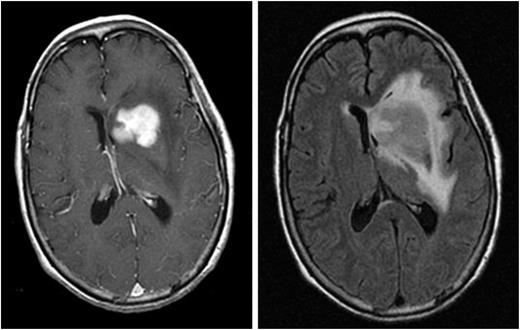

Neurocognitive symptoms are the most common presenting clinical features of PCNSL. The International PCNSL Collaborative Group (IPCG) has developed guidelines to determine extent of disease.7  A gadolinium-enhanced brain magnetic resonance imaging (MRI) scan is the most sensitive radiographic study for the detection of PCNSL (Figure 1). Most PCNSL patients present with a single brain mass. The diagnosis of PCNSL is typically established by stereotactic brain biopsy, cerebrospinal fluid (CSF) analysis, or by analysis of vitreous aspirate in patients with ocular involvement. Given the possible delay in diagnosis and treatment with the latter 2 methods, prompt stereotactic biopsy is advised in almost all cases that are surgically accessible. Corticosteroids have lymphotoxic effects and should be avoided, if possible, before stereotactic biopsy as a histopathologic diagnosis can be difficult or impossible to achieve after exposure to these drugs. Secondary CSF and ocular involvement occurs in ∼15% to 20% and 5% to 20% of PCNSL patients, respectively. Presenting symptoms of ocular involvement include eye pain, blurred vision, and floaters.8  B symptoms such as weight loss, fevers, and night sweats are infrequent in PCNSL. A thorough diagnostic evaluation is needed to establish the extent of the lymphoma and to confirm localization to the CNS. A lumbar puncture should be performed if not contraindicated, and CSF should be assessed by flow cytometry, cytology, and immunoglobulin heavy-chain gene rearrangement. Because extraneural disease must be excluded to establish a diagnosis of primary CNS lymphoma, computed tomography/positron emission tomography scans of the chest, abdomen, and pelvis, and a bone marrow biopsy and aspirate should be performed to exclude occult systemic disease. Involvement of the optic nerve, retina, or vitreous humor should be excluded with a comprehensive eye evaluation by an ophthalmologist that includes a slit-lamp examination. Blood tests should include serum lactate dehydrogenase and HIV serology.7

Figure 1.

Magnetic resonance images from a patient with PCNSL. A T1-weighted, axial, postcontrast scan (left) demonstrates intense, homogenous enhancement of the tumor in the region of the left caudate nucleus. An axial T2/FLAIR scan at the same anatomical level (right) demonstrates hyperintense signal surrounding the tumor, reflecting vasogenic cerebral edema. (Courtesy Priscilla K. Brastianos, M.D.)